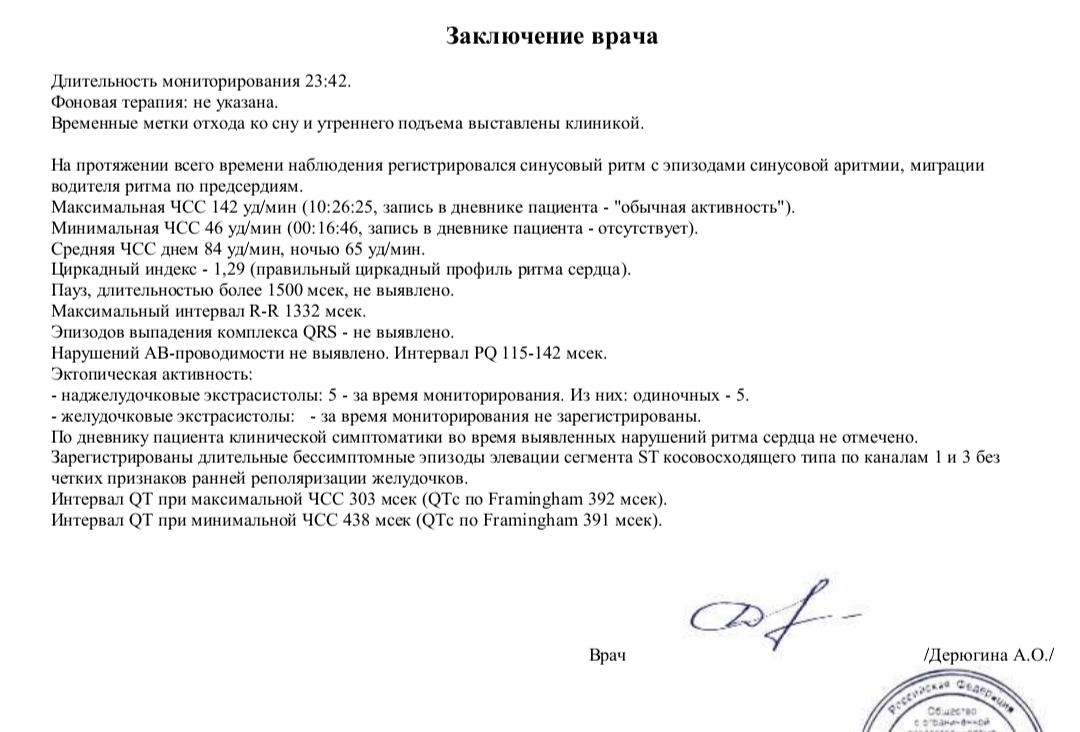

Расшифровка результатов холтера

|

|

👍 0 👎 |

Есть ли изменения по холтеру и вэг?

|